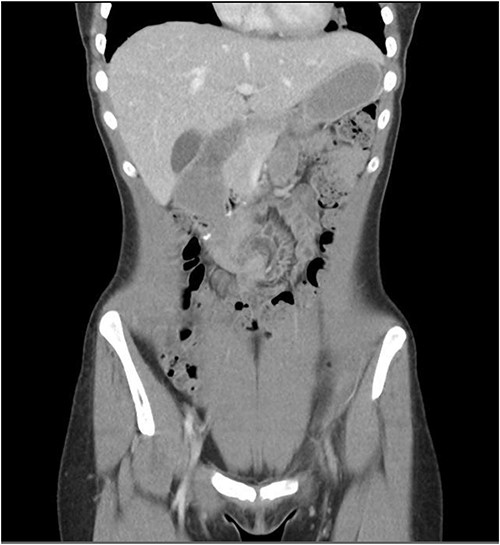

The patient was taken for a diagnostic laparoscopy and found to have an internal hernia. Small bowel had fallen through a defect between the afferent limb of the jejunum and the third part of the duodenum (Fig. 3). This was reduced, the small bowel was run and found to be viable with no need for resection. The defect was closed with 3.0 V-lock suture.

A duodenojejunostomy involves creating an anastomosis between the duodenum and the jejunum [4]. A review of what literature is available on duodenojejunostomy for SMA syndrome reports that most surgeon’s anastomosis the jejunum 20–30 cm from the DJ flexure [5]. Internal hernias are a very rare complication of a duodenojejunostomy and there is no literature on this phenomenon. This patient’s anastomosis occurred at 60 cm from the DJ flexure, which may have created a bigger defect and therefore made this patient more prone to an internal hernia.